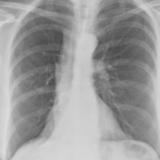

Gallery Lobar Collapse

Lobar Collapse

LUL Collapse

Album: LUL Collapse

LLL Collapse

Album: LLL Collapse

RLL Collapse

Album: RLL Collapse

RUL Collapse

Album: RUL Collapse

RML Collapse

Album: RML Collapse